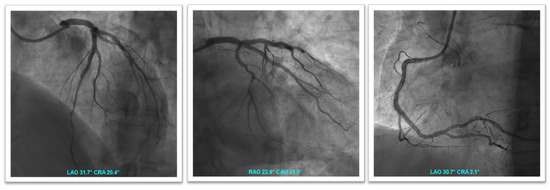

1.3. Patient 3

1.4. Patient 4